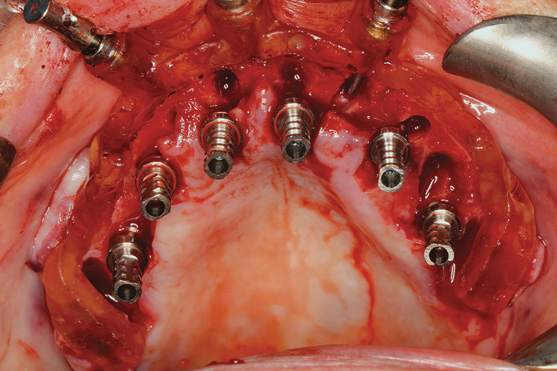

The workflow described in this case is just one example, and there are numerous ways to achieve the same goal. This particular workflow is relatively easy to execute and efficient from the standpoint of planning, fabrication, and clinical application. Figure 11 and Figure 12 demonstrate the accurate placement of the implants as can be seen by the copings exiting directly into the openings in the printed provisional. The provisional was indexed and the copings picked-up by injecting a provisional bisacryl composite resin. The finished 3D-printed provisional was characterized with pink composite and fixated to the implants with abutment screws, and the access holes were sealed with sterilized teflon tape and composite resin (Figure 13).

Fig 11. Implants with telescopic copings ready for pick-up.

Figure 11